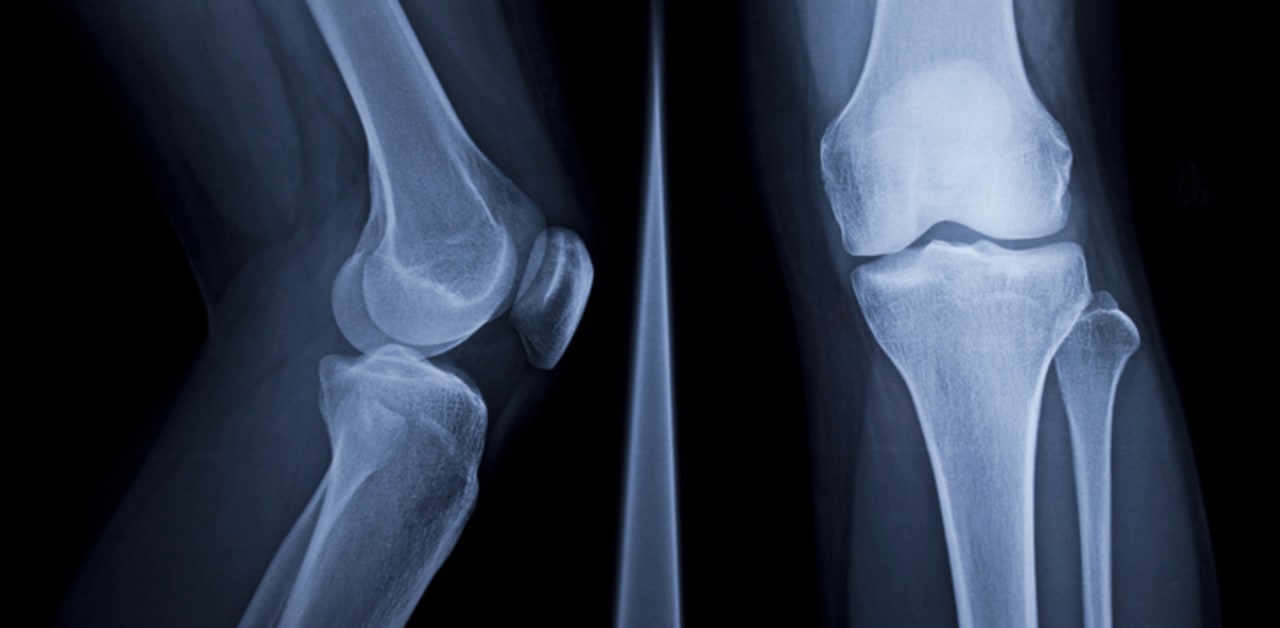

A 2025 scoping review in BJR Open highlights the transformative role of artificial intelligence (AI) in musculoskeletal (MSK) radiology, led by Dr. Mickael Tordjman from Icahn School of Medicine. The review outlines AI applications across seven key areas: accelerated image acquisition, enhanced interpretation, large language models (LLMs), workflow integration, cost-effectiveness, liability concerns, and education. With early emphasis on fracture detection, AI has expanded to include deep learning-based reconstruction and automated classification of bone lesions, improving diagnostic accuracy and efficiency. Notably, AI applications can reduce scan times by up to 53% while maintaining image quality. LLMs streamline report generation, supporting communication among radiologists, clinicians, and patients. Successful AI adoption depends on seamless integration into existing systems, regulatory compliance, and proof of cost-effectiveness. Ultimately, AI serves best as an assistive tool, enhancing radiologist capabilities rather than replacing them. Clear guidelines are essential for safe, responsible implementation.